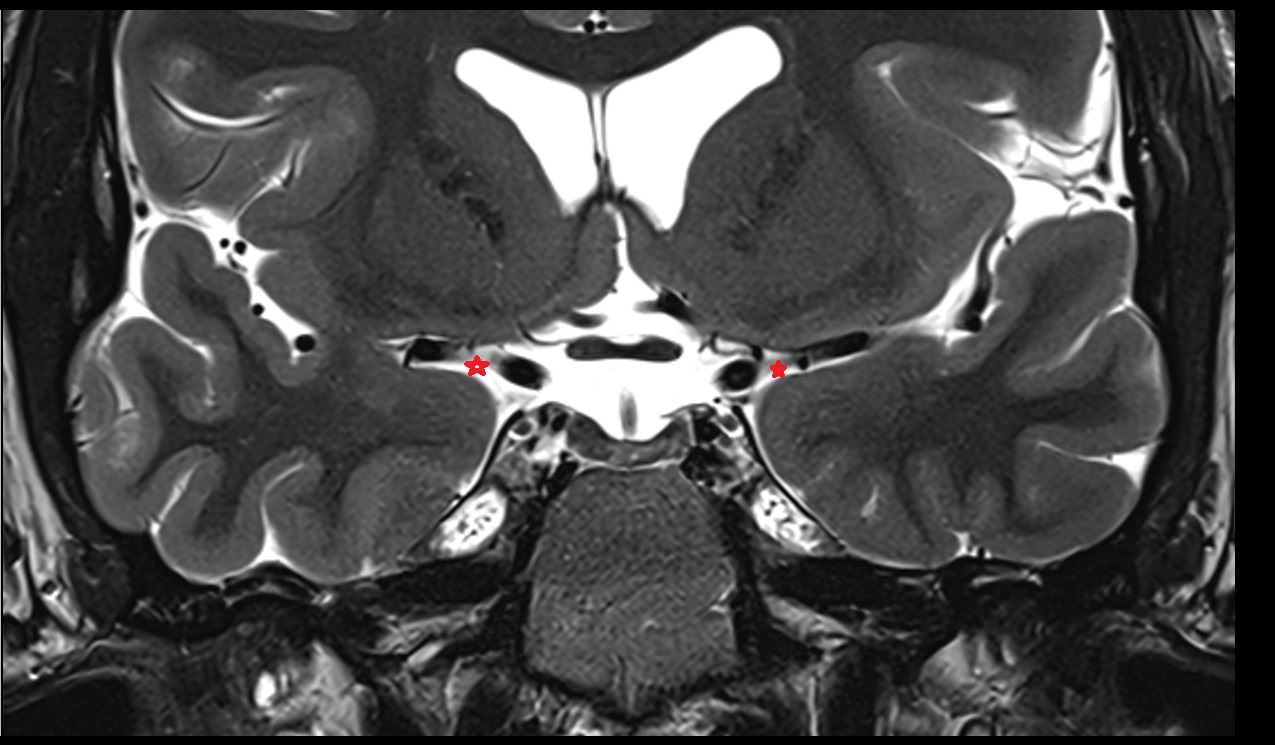

- Lateral aperture of fourth ventricle (foramen of Luschka)